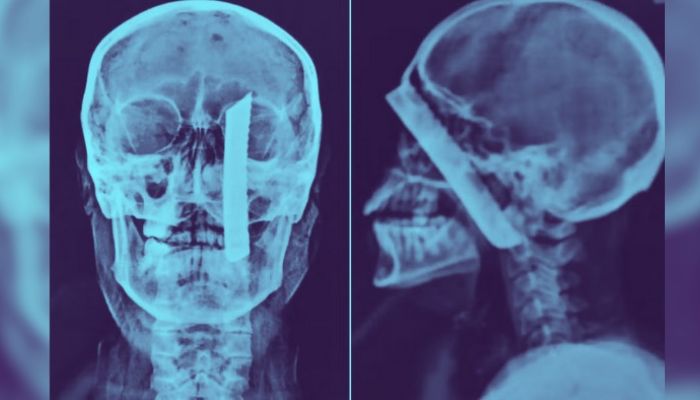

Segundo informações, a vítima teve uma lâmina cravada em sua cabeça, conforme evidenciado por imagens do exame de raios-x. O crime aconteceu em 27 de outubro do ano passado, no bairro Balneário Regina Maria.

A vítima foi inicialmente levada à Unidade de Pronto Atendimento (UPA) de Agenor de Campos, onde realizou exames para avaliar a extensão do ferimento. Devido à gravidade, foi transferida para o Hospital Irmã Dulce, onde passou por cirurgia.